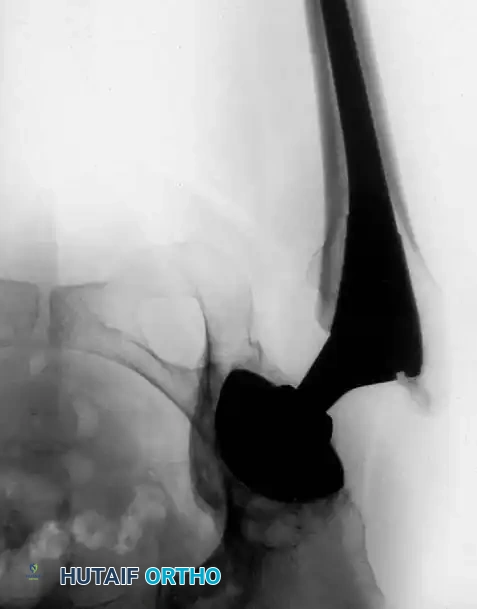

Radiographic Case Examples: Osteoarthritis and Complex Reconstructions

The following imaging series demonstrates various stages of complex acetabular and femoral preparation, highlighting the necessity of restoring offset and center of rotation.

Preoperative templating demonstrating severe joint space narrowing and lateral subluxation.

Intraoperative fluoroscopy confirming initial reamer positioning.

Assessment of the medial wall following osteophyte resection.

Trialing of the acetabular component to ensure adequate superior coverage.

Final seating of the cementless acetabular shell with supplemental screw fixation.

Postoperative AP pelvis showing restored offset and anatomic hip center.